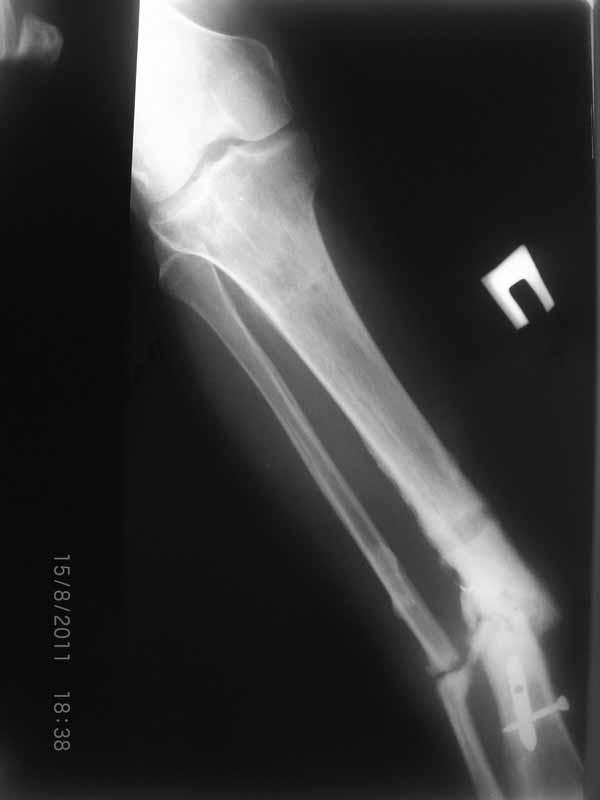

Это гипотрофический ложный сустав. Проблем видится несколько:

1. нарушение трофики в месте перелома.

2. после фиксации в аппарате Илизарова на рентгеногнрамме имеются признаки спицевого остеомиелила. В настоящи момент хотя свищей нет с мая 2011 нет опасно ли фиксировать голень стержнем?

На основании каких признаков Вы решили, что кость мертвая! Имеется гиперпластический ложный сустав, как результат недостаточно стабильной фиксации ан предыдущих этапах лечения. В данном случае необходимо решение следующих вопросов:

Место ложного сустава не выглядит гипертрофическим. Нет разрастания костной мозоли.